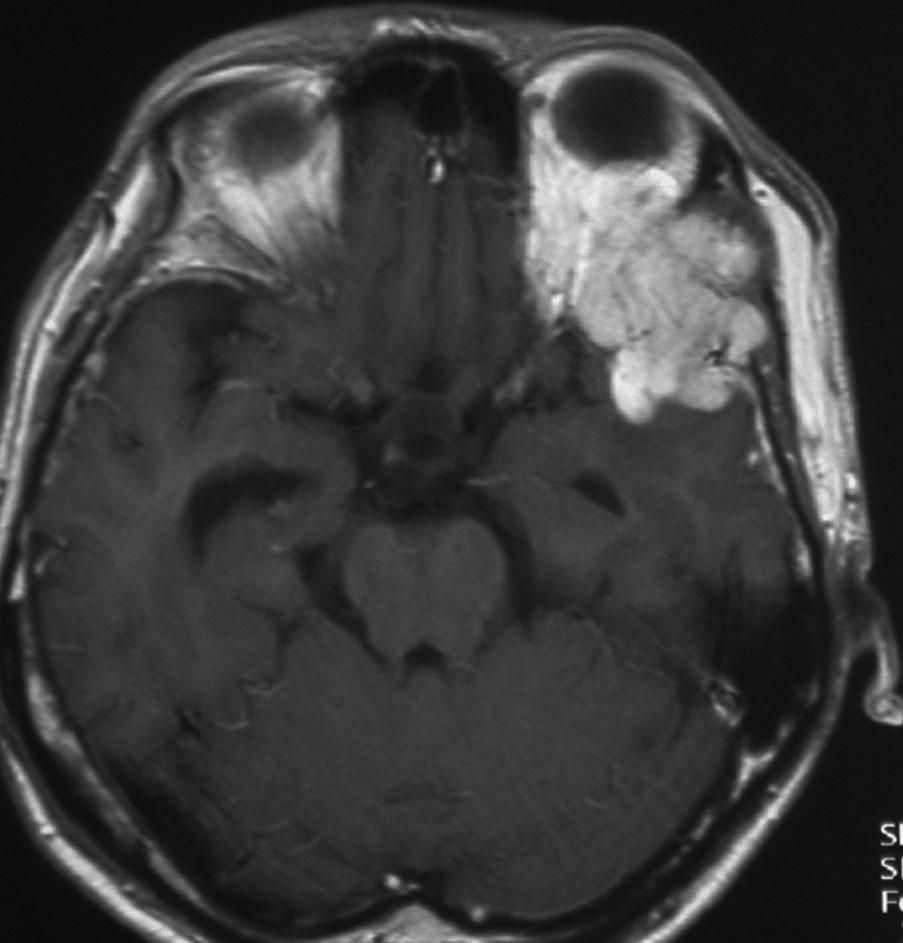

1984年 19歳の時に,松果体のジャーミノーマに全脳照射45グレイで治療されました(左CT)。1997年左蝶形骨縁にヘマンジオペリサイトーマが発生しました(中央と右のMRI)。手術で全摘出しましたが4年後,2001年に脊髄に播種再発してつらい経過を辿りました。眼窩壁を破る典型的なヘマンジオペリサイトーマの像で,放射線誘発髄膜腫との鑑別がとても大切なものです。